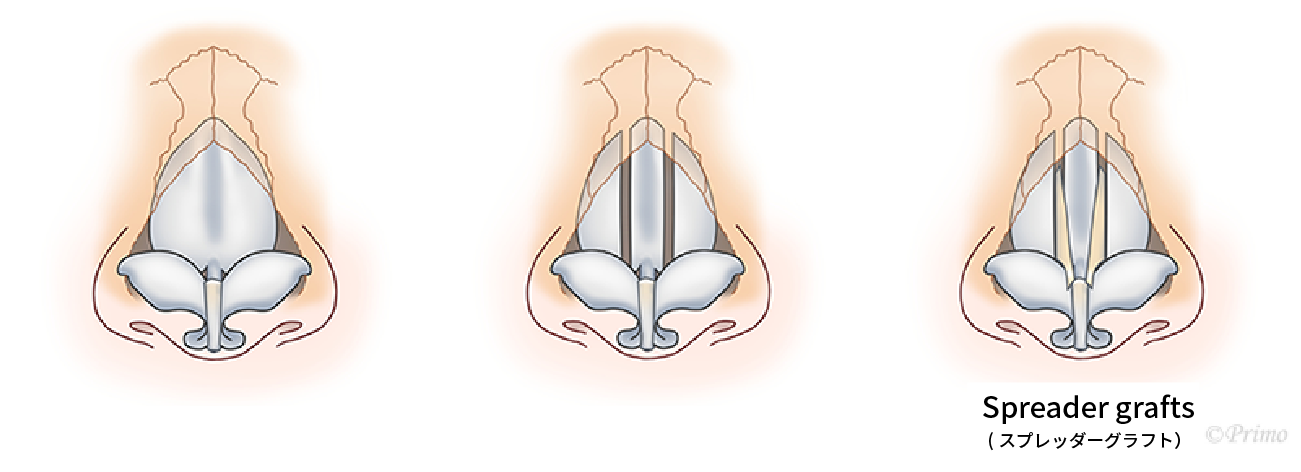

斜鼻の修正について鼻が曲がっているのを治したがまだ曲がりが気になる場合、鼻中隔軟骨の傾きや方向が原因であることがしばしばあります。鼻中隔矯正術を行い、可能な限りまっすぐな状態に形成いたします。斜鼻によって鼻閉が起きている場合には、下鼻甲介粘膜下骨切除術をおこなったり、spreader graft手術を同時に用いるなどで鼻腔を広げるように形成いたします。

両側にspreader graftとして用いることもあります。

よりしっかりと矯正でき、鼻腔通気も改善するため鼻閉の治療にもなる方法です。